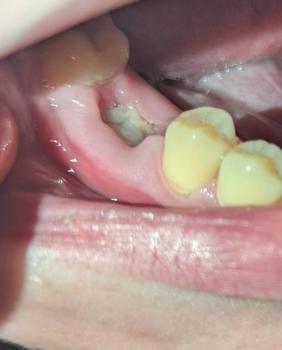

Getting a dental implant after a tooth extraction is one of the most common questions patients ask. The timing depends on your healing, bone condition, and overall oral health.

There are three main options: